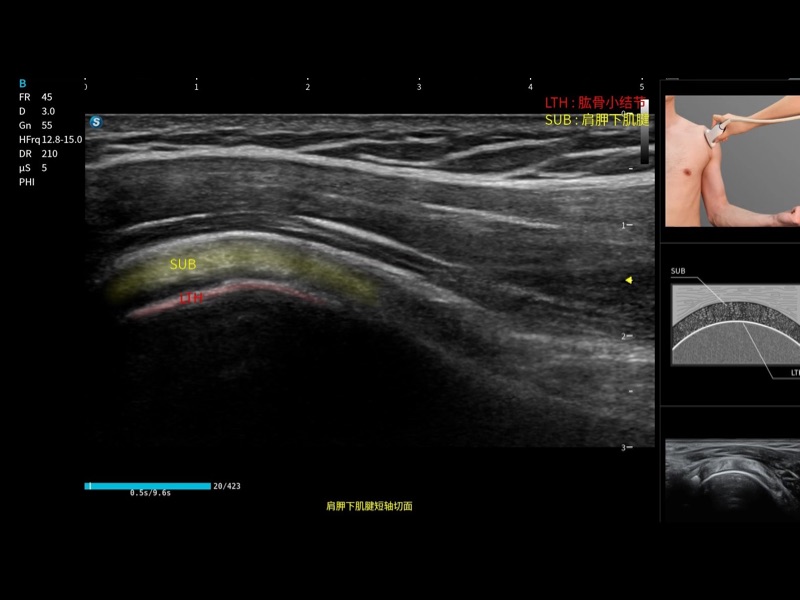

作为开立医疗全新打造的高端床旁笔记本超声,E11不仅具备卓越的图像质量,同时搭载全面高效的自动测量工具,助力医生实现更快速、更精准的床旁诊断。

E11搭载了丰富的自动化测量工具,以及专为POC科室定制的高级功能;同时配备了为急诊医师量身打造的 SonoFast急重症超声流程,以帮助临床医生最大限度的提升工作效率